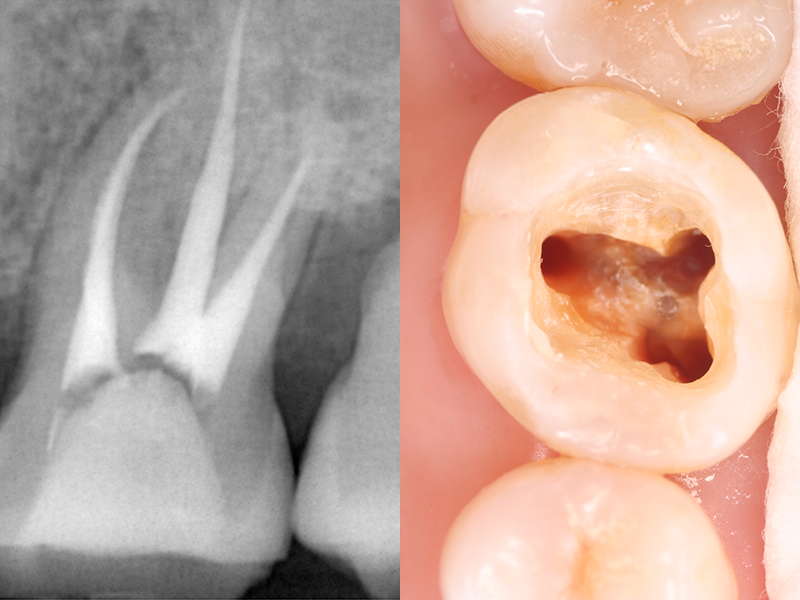

歯の内部には「歯髄(しずい)」と呼ばれる神経や血管を含む組織があります。進行したむし歯や外傷によって、歯髄が細菌に感染したり壊死した場合には、歯髄を除去するための「根管治療」が必要です。

根管治療とは、細菌によって汚染された根の内部を細い器具(ファイル)で丁寧に除去し、洗浄・消毒を行うことで、根管内の痛みや炎症を抑える治療です。治療後は、根管内に薬剤を充填し、かぶせ物やつめ物を装着することで、歯の機能を再び取り戻します。

根管治療用の器具を使って、感染している歯質や残っている歯髄などを除去します。